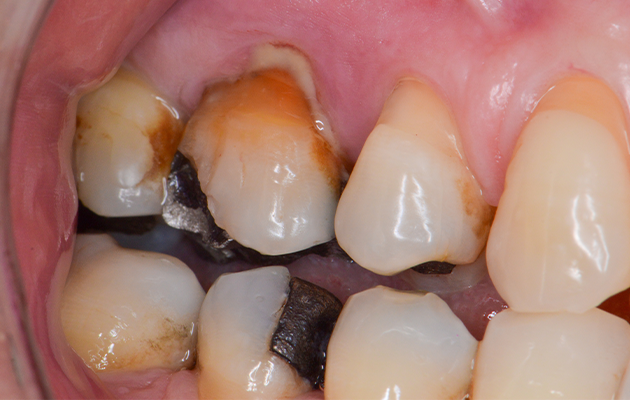

Na avaliação clínica, verificou-se o extravasamento de pus via sulco gengival no dente 16. A paciente relatava dor à palpação local e durante a percussão. Além disso, o dente 16 apresentava mobilidade grau 1, fratura de cúspides, uma extensa restauração de amálgama, lesões cariosas próximas à restauração e acúmulo de biofilme. O exame tomográfico revelou uma lesão envolvendo a raiz mesiovestibular do dente 16, com provável comunicação endoperiodontal.

1 | Aspecto inicial do dente 16. Destaque para a supuração drenada via sulco gengival